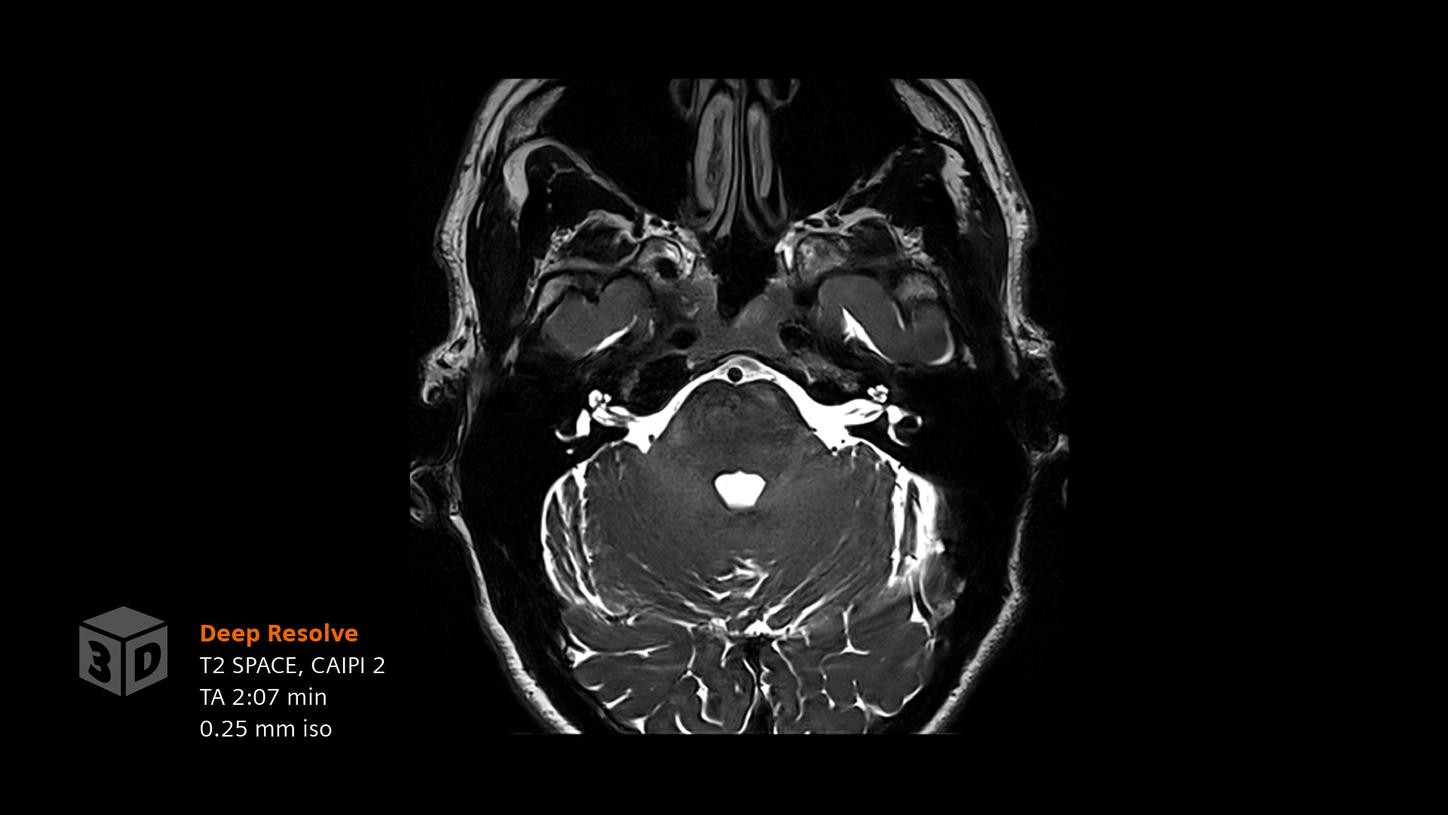

Deep Resolve will be at the forefront of the revolution in MRI acceleration. Deep Resolve will enable our fastest MRI, with images that will have extraordinary clarity, higher clinical productivity, and an even better patient experience. This transformational effect of Deep Resolve is now planned to expand to 3D5, unlocking a new dimension in MRI image resolution and speed.

More about Deep Resolve